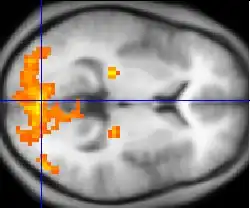

An example of an fMRI brain scan

In 2018 a study examined volunteers' brains under experimentally induced déjà vu through the use of fMRI brain scans. The induced "deja vu" state was created by getting them to look at a series of logically related and unrelated words. The researchers would then ask the participants how many words starting with a specific letter they saw. With related words such as "door, shutter, screen, breeze", the participants would be asked if they saw any words that started with "W" (i.e. Window, a term that was not presented to the participants). If they did note that they thought they saw a word that wasn't presented to them, then déjà vu was induced. The researchers would then examine the volunteers' brains at the moment of induced déjà vu. From these scans, they noticed that there was visible activity in regions of the brain associated with mnemonic conflict. This finding suggests that more research regarding memory conflict may be important in better understanding déjà vu.[38]